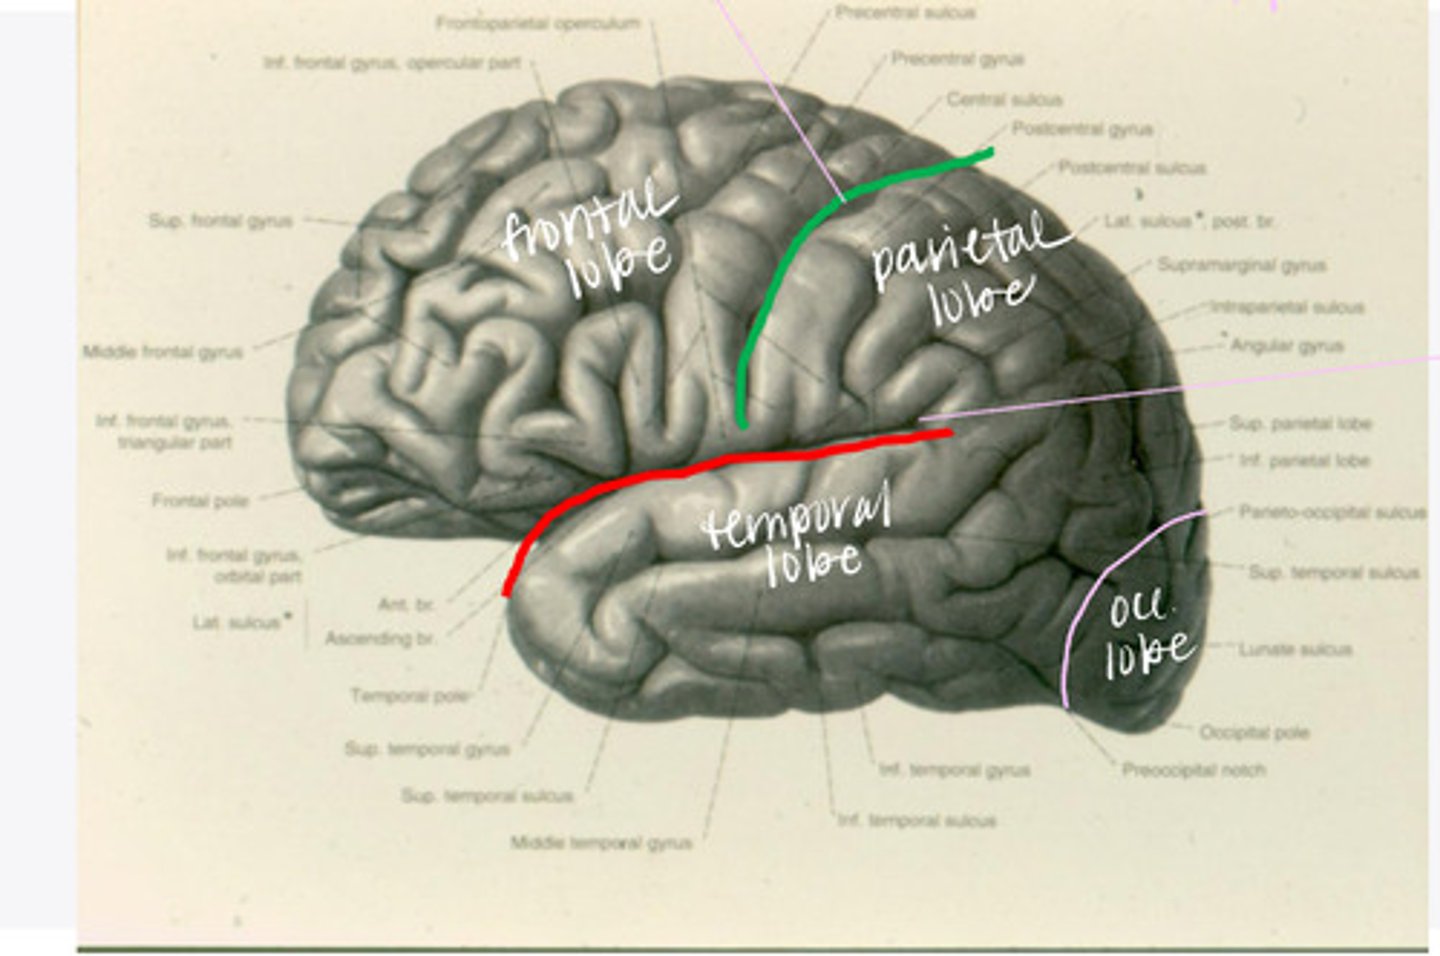

-frontal

-parietal

-temporal

-occipital

What are the 4 lobes of the brain?

central sulcus

What sulcus differentiates the frontal from the parietal lobe?

lateral sulcus

What sulcus differentiates the frontal from the temporal lobe?

The frontal lobe is divided into what 4 gyri?

What are the 3 divisions of the inferior frontal gyrus?

-post-central gyrus

-superior parietal lobule

-inferior parietal lobule

What are the divisions of the parietal lobe?

-supramarginal gyrus

-angular gyrus

What are the divisions of the inferior parietal lobule?

-superior temporal

-inferior temporal

What are the 2 major sulci of the temporal lobe (on lateral view)?

-superior temporal

-middle temporal

-inferior temporal

What are the 3 major gyri of the temporal lobe (on lateral view)?

everything posterior to the line connecting the parietooccipital sulcus and the preoccipital notch

Where is the occipital lobe located in a lateral view of the brain?